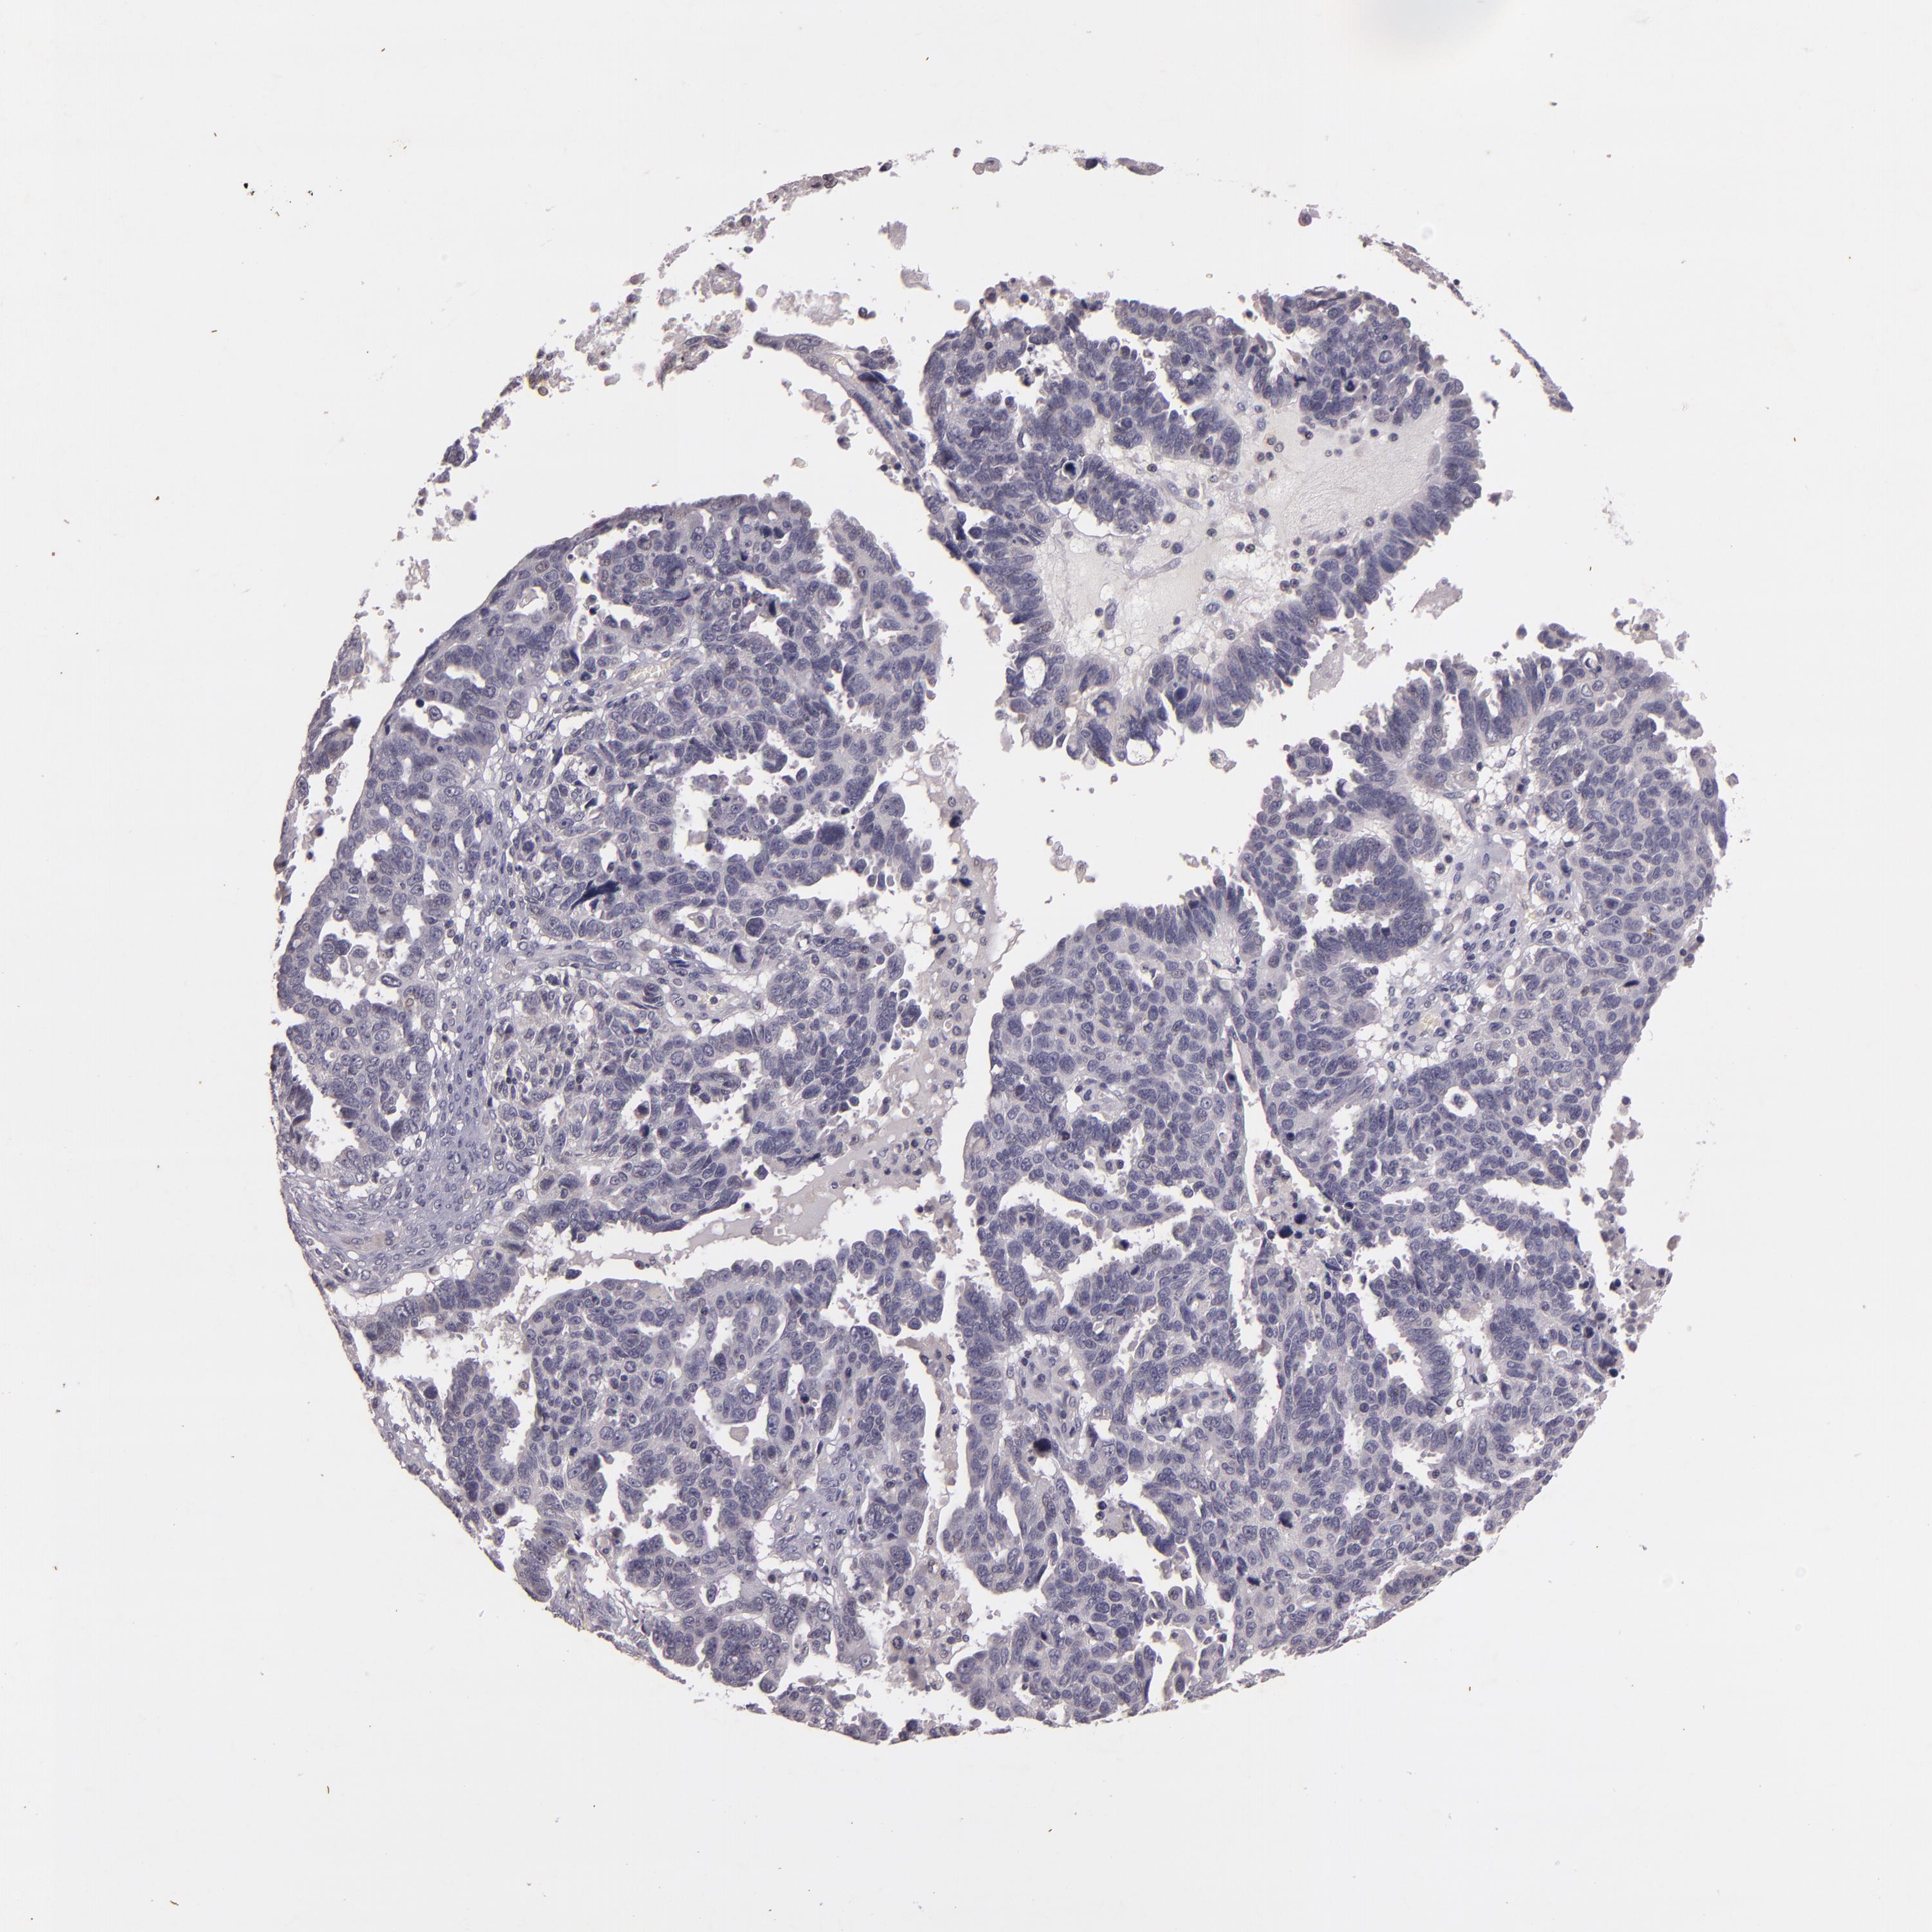

OVARIAN CANCER - Protein expressioni

A mouse-over function shows sample information and annotation data. Click on an image to view it in a full screen mode. Samples can be filtered based on level of antibody staining by selecting one or several of the following categories: high, medium, low and not detected. The assay and annotation is described here.

Note that samples used for immunohistochemistry by the Human Protein Atlas do not correspond to samples in the TCGA dataset.

Antibody stainingi

Antibody staining in the annotated cell types in the current human tissue is reported as not detected, low, medium, or high, based on conventional immunohistochemistry profiling in selected tissues. This score is based on the combination of the staining intensity and fraction of stained cells.

Each image is clickable and will lead to virtual microscopy that enables deeper exploration of all samples and also displays staining intensity scores, fraction scores and subcellular localization as well as patient and tissue information for each sample.

Antibody HPA003425

Antibody CAB002170

Cystadenocarcinoma, serous, NOS

Cystadenocarcinoma, mucinous, NOS

Carcinoma, endometroid